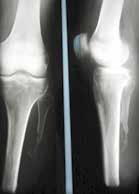

Sehr lange Unterschenkelstümpfe (kurz oberhalb der Spongiosa der distalen Tibia) sind auf die Dauer wegen der Gefahr zunehmender trophischer Störungen über die Jahre auch bei sehr geringem Endkontakt in der Prothese problematisch (Abb. 11). Viele Jahre scheint ein langer US-Stumpf gut versorgbar zu sein, wenn die Amputation im Kindesalter stattfindet und wenn Tibia- und Fibulaende sich fast auf gleicher Höhe befinden und somit eine breitere Auflagefläche für den Endkontakt darstellen (Abb. 12). Gewebe und arterielle Durchblutung stellen sich offenbar im Kindesalter auch besser auf die Gesamtsituation ein. Allgemein gilt aber: Der beste Unterschenkelstumpf ist der, der mit Muskulatur unter physiologischer Vorspannung gedeckt ist.